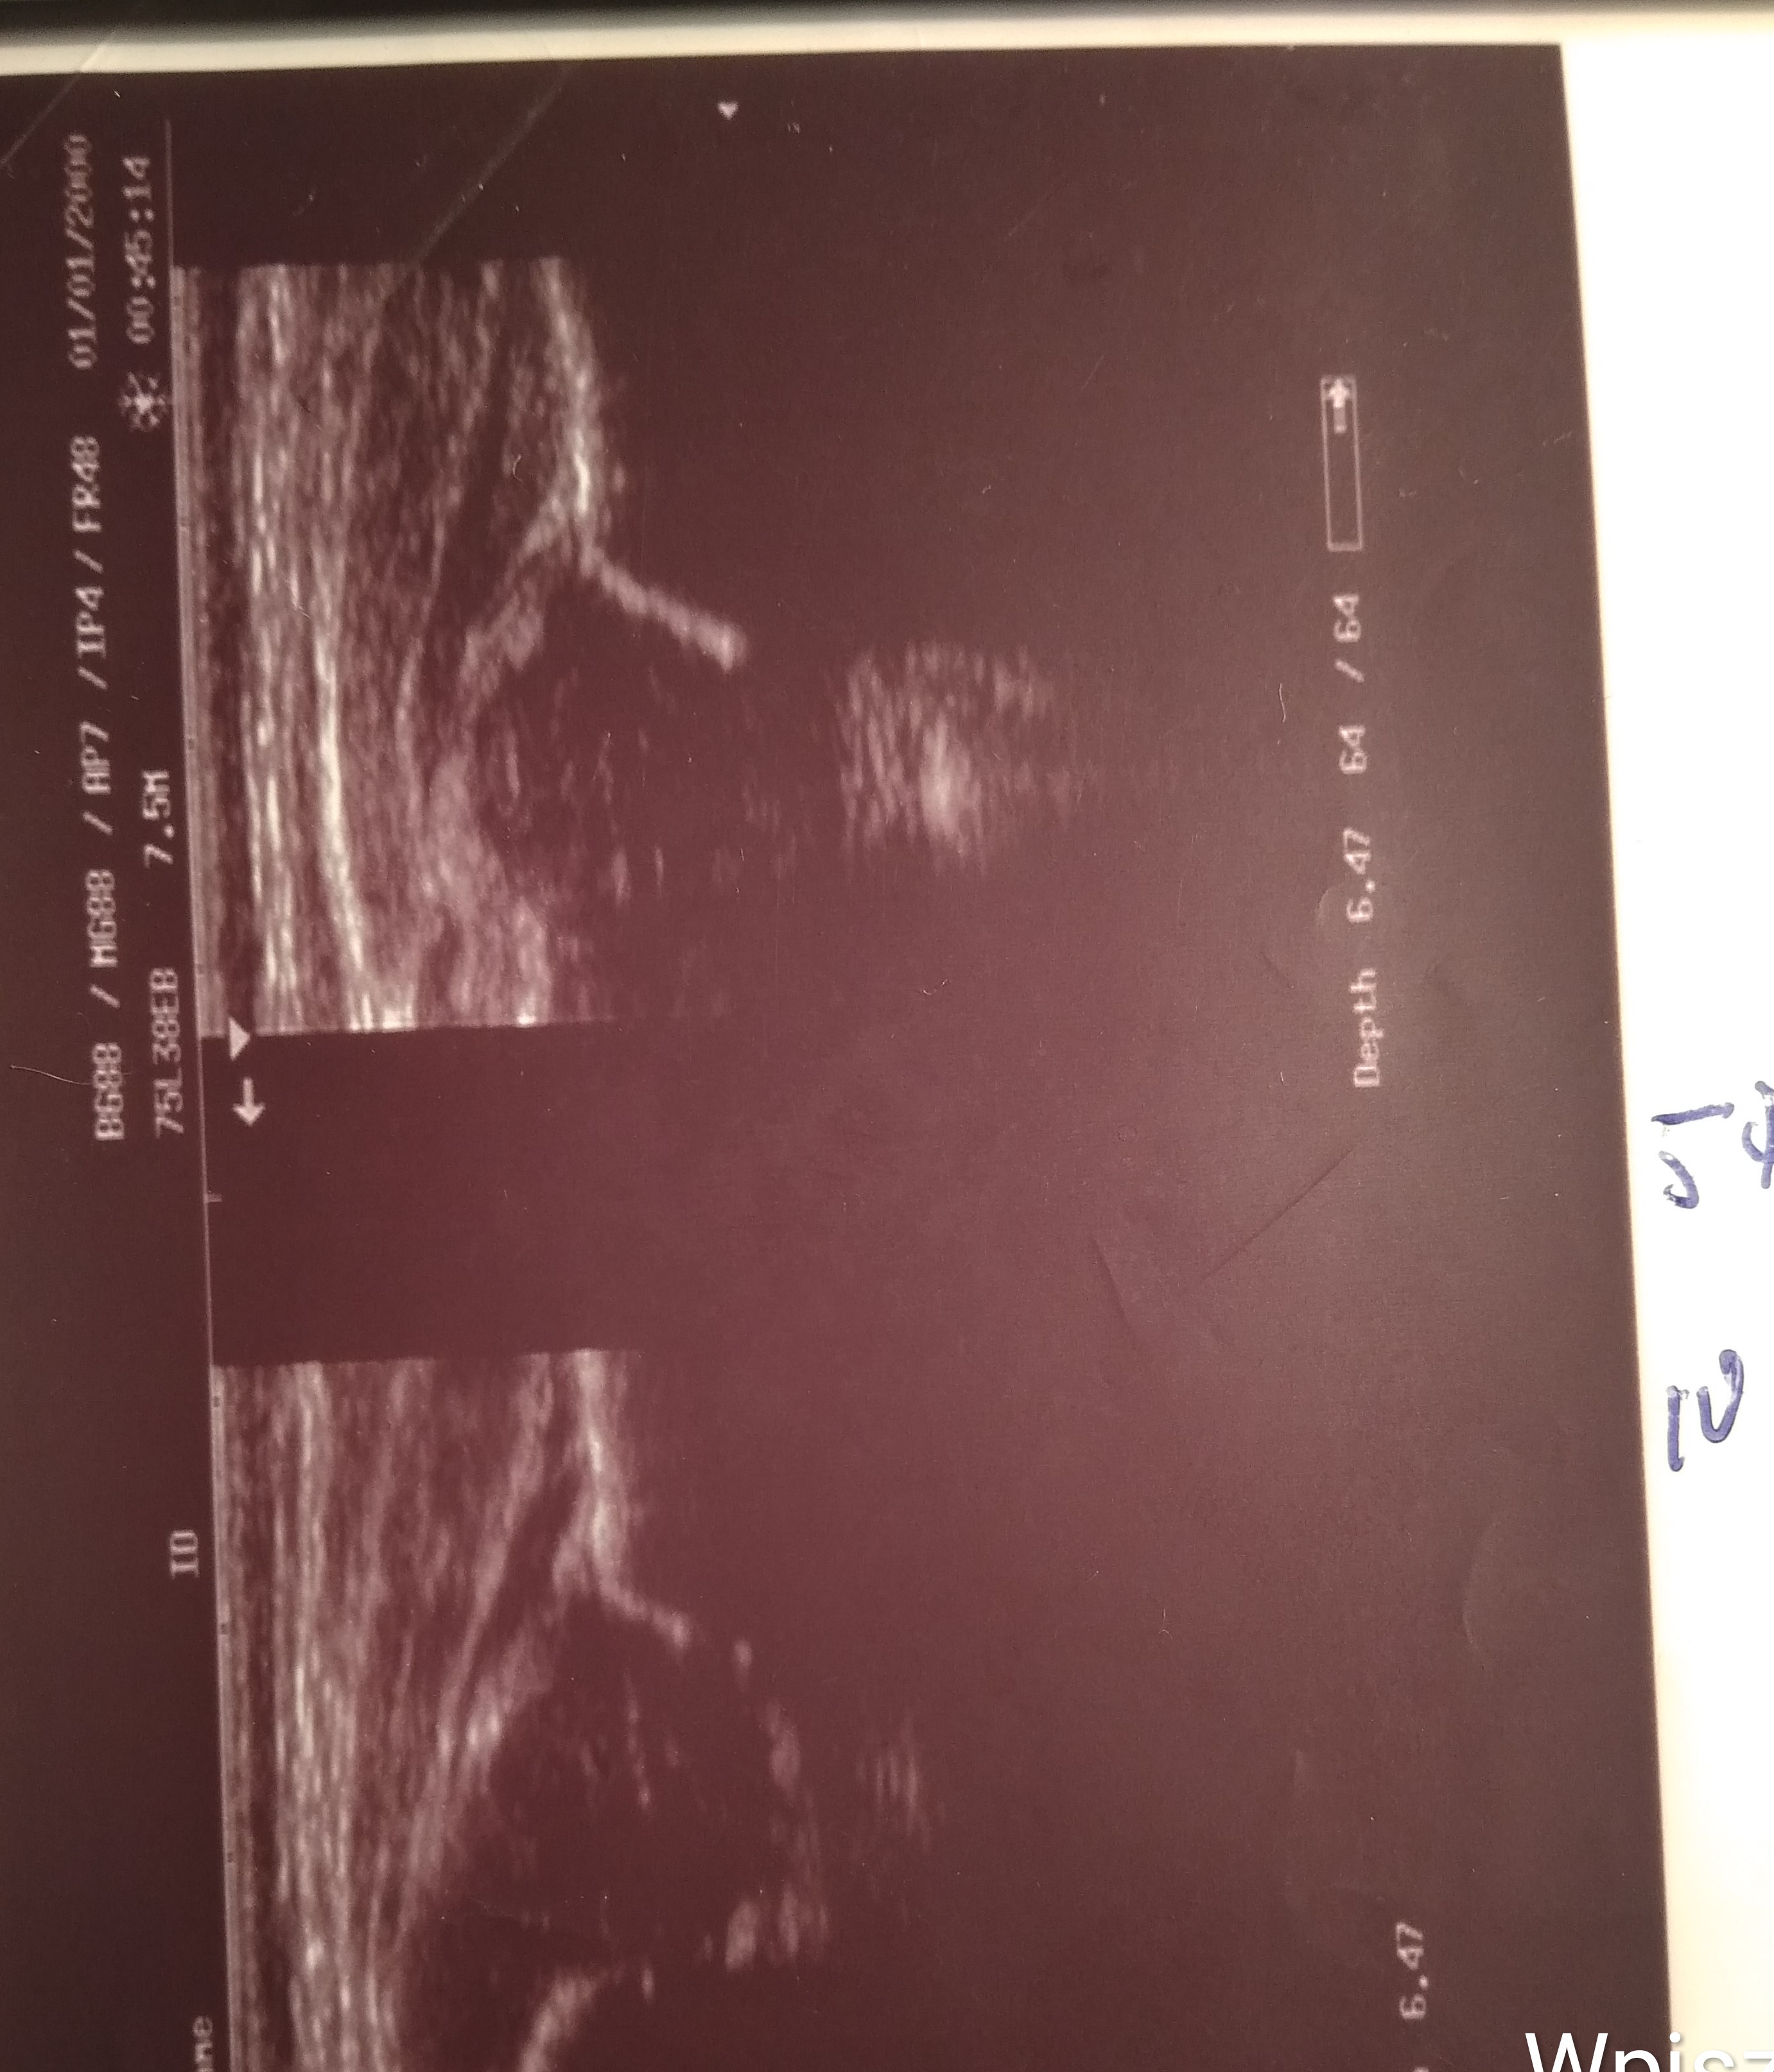

7 dzien zycia środa dzien póżniej Typ P IIIa L D widac juz poprawe dalej profilaktyka kontrola w nastepnym dniu

8 dzien czwartek protilaktyka dalej 24 godz na dobę